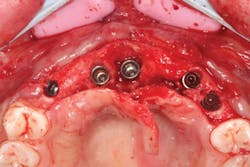

The patient was sedated intravenously in a surgically sterile in-office operatory. The surgical guide was placed over the teeth, checked to make sure it was fully seated without soft tissue impingement or surgical guide excess (figure 5). It was verified that there was no rocking of the guide from either side. An initial pilot drill was made through the guide into the soft tissue. A surgical incision was made with a 15c blade splitting across the keratinized gingiva across the crest of the ridge from Nos. 5–11. A full-thickness flap was elevated buccally and lingually. This released the soft tissue enough to allow the implant drills to go to depth and perform a widening osteotomy. Five osteotomies were made with copious saline irrigation and drill speed of 2,000 rpm. A pilot drill and each sequential step drill guide were used to widen out the osteotomy before placing five 3.5 mm x 10.5 mm MegaGen AnyRidge implants (figure 6). The implants were placed and torqued out at 35 Ncm. (Implants were not placed through the guide, although this was an option. Cover screws were placed. A bone graft with fusion bone binder (figure 7) and platelet-rich fibrin (PRF) were all placed over the implants before suturing with 5.0 polyglycolide sutures (figure 8). The upper partial was relined to take pressure off the soft tissue site.

Figure 6: Implants placed